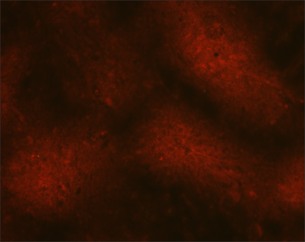

Rabies serology

Two serological assays are considered acceptable for detecting rabies virus neutralizing antibodies: Rapid Fluorescent Focus Inhibition Test (RFFIT) and Fluorescent Antibody Virus Neutralization (FAVN) test. These assays cannot differentiate between an antibody response to vaccination or as a result of infection.

- Detection of neutralizing antibodies in cerebrospinal fluid or the serum of an unvaccinated individual is considered a positive test for rabies virus infection

- RFFIT (human and animals) and FAVN (animals) are also used to confirm an adequate vaccination response. A serological titer greater than or equal to 0.5 international units per milliliter is considered evidence of an adequate immune response.

The indirect immunofluorescence assay (IFA) detects binding antibodies against rabies virus encoded proteins and can be an early indication of rabies virus infection in humans. This test is only used as part of antemortem rabies testing in humans. IFA test has the advantage of detecting isotype specific response, i.e. IgM and IgG antibodies.